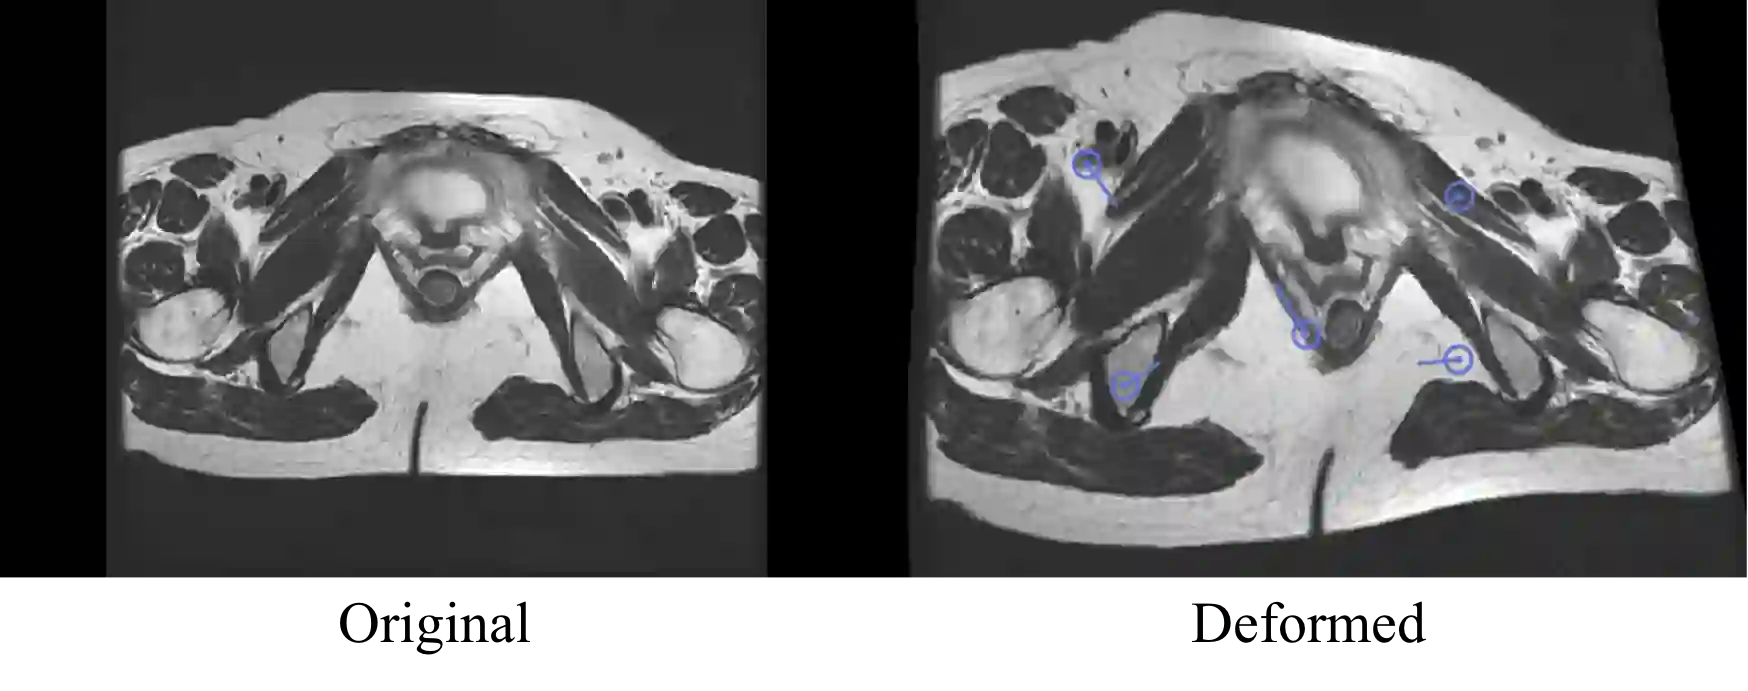

One of the time-consuming routine work for a radiologist is to discern anatomical structures from tomographic images. For assisting radiologists, this paper develops an automatic segmentation method for pelvic magnetic resonance (MR) images. The task has three major challenges 1) A pelvic organ can have various sizes and shapes depending on the axial image, which requires local contexts to segment correctly. 2) Different organs often have quite similar appearance in MR images, which requires global context to segment. 3) The number of available annotated images are very small to use the latest segmentation algorithms. To address the challenges, we propose a novel convolutional neural network called Attention-Pyramid network (APNet) that effectively exploits both local and global contexts, in addition to a data-augmentation technique that is particularly effective for MR images. In order to evaluate our method, we construct fine-grained (50 pelvic organs) MR image segmentation dataset, and experimentally confirm the superior performance of our techniques over the state-of-the-art image segmentation methods.